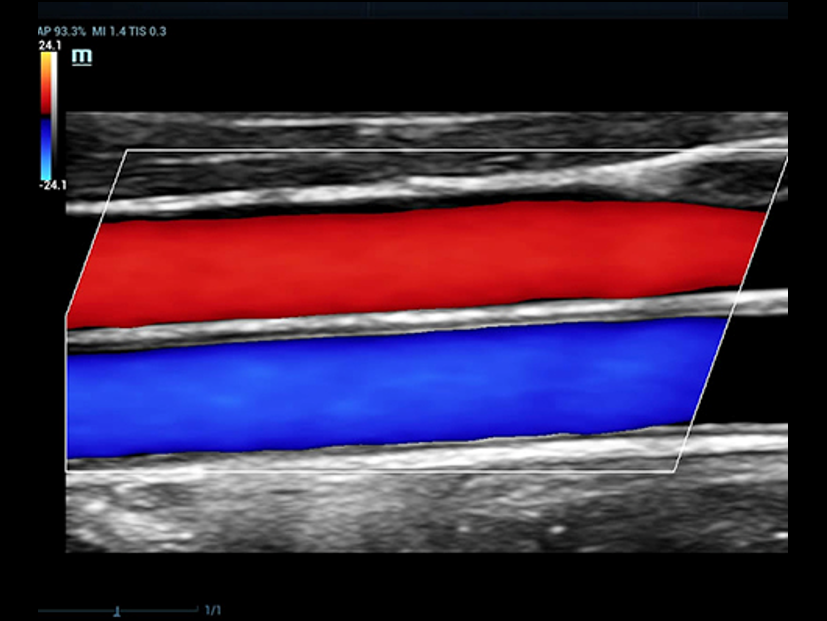

- El modelo Resona 7 es un sofisticado ecógrafo Dopple Color, fue diseñado con la tecnología Zone Sonography, el cual es capaz de transformar la forma tradicional de procesamiento de señales en formación de haces en datos de canal.

- Este modelo es capaz de mejorar las capacidades de investigación clínica por medio de la tecnología de evaluación hemodinámica vascular, V Flow.